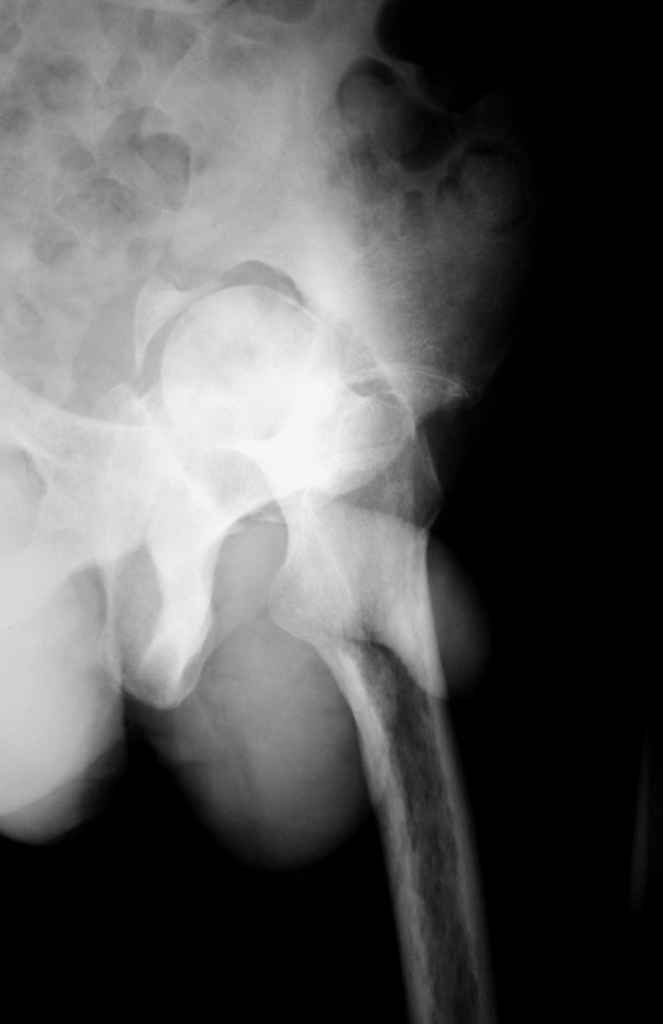

К сожалению, нередкая ситуация, мы предпочитаем выполнять операцию одномоментно - пластика задне-верхнего дефекта крыши ВВ собственной

головкой, установка вертлужного компонента бесцементной фиксации с обязательной дополнительной фиксацией винтами. Проблема будет в

восстановлении длины ноги, опыт показывает, что более 3-х см одномоментно восстановить очень сложно, и даже для этого потребуется широкая мобилизация бедра. В одном из номеров ж-ла Ортопедия травматология России мы опубликовали наш подход и р-ты лечения у больных с последствиями перелома ВВ.

Прилагаю в качестве иллюстрации одну из последних операций.